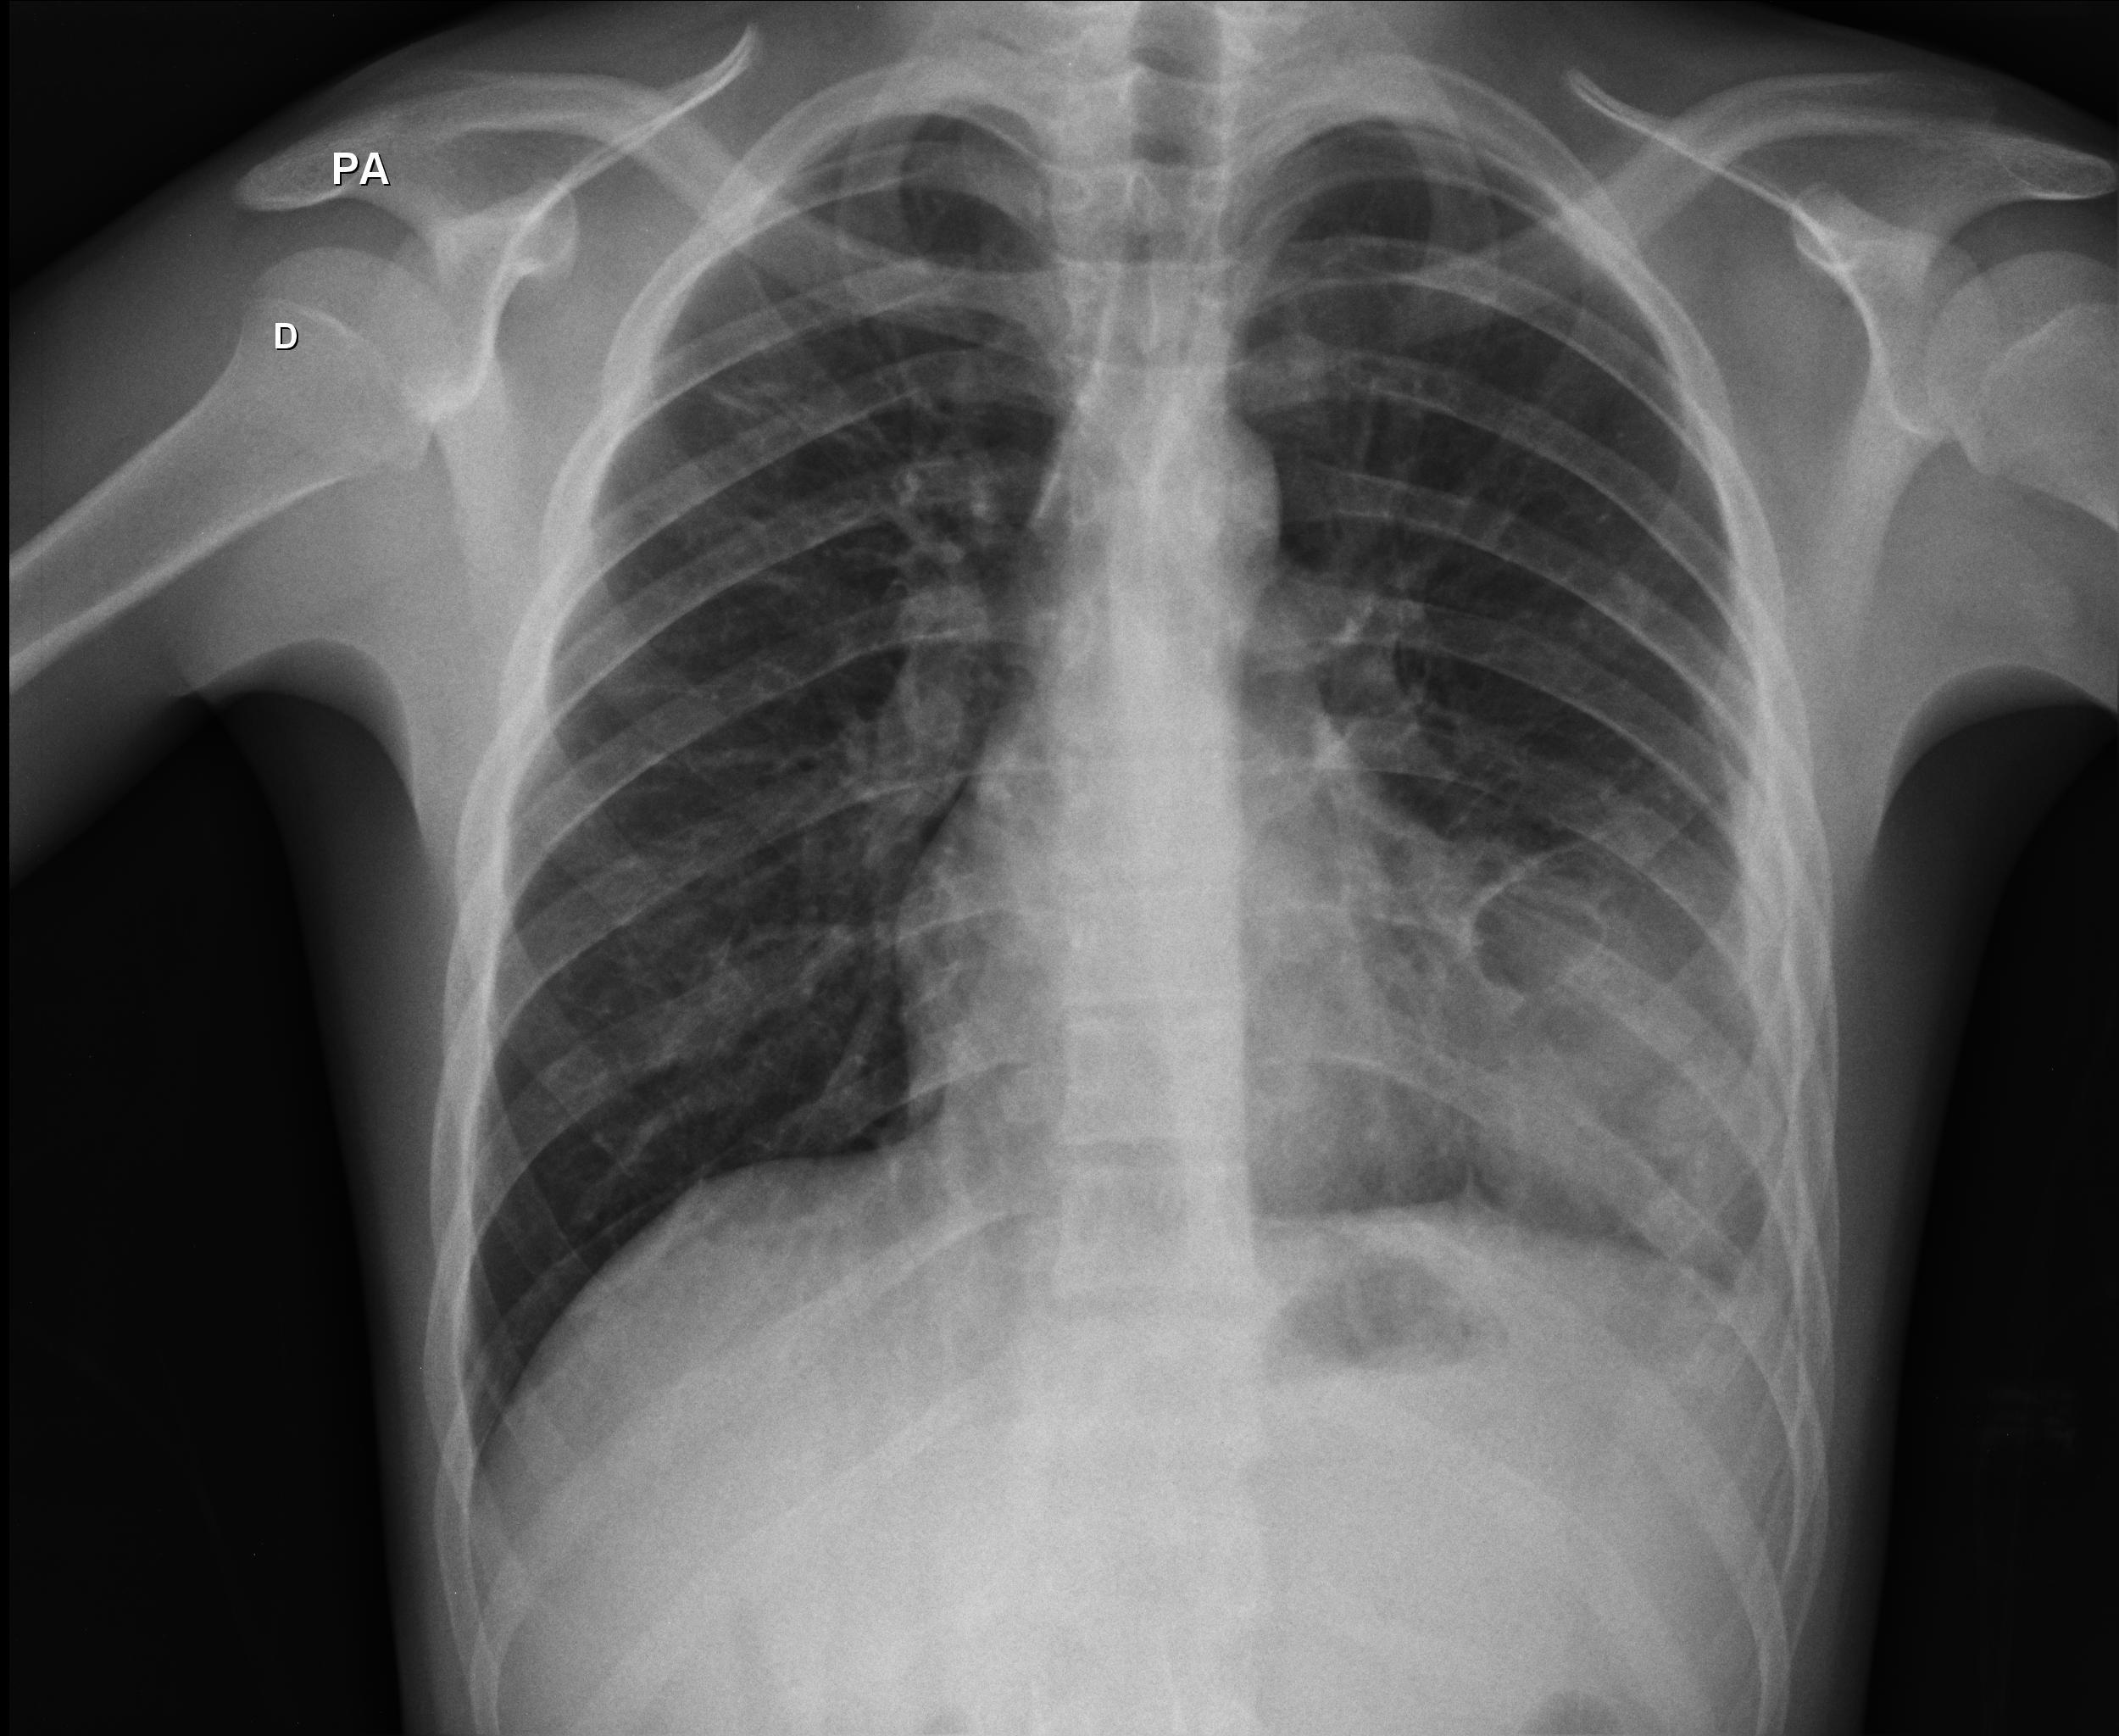

Caso relatado na Reunião de Discussão de Casos Clínicos do Hospital Universitário Prof. Polydoro Ernani de São Thiago, iniciada pelos Profs. Jorge Dias de Matos, Marisa Helena César Coral e Rosemeri Maurici da Silva, em julho de 2017. No dia 14 de junho de 2018, no auditório do HUPEST, realizou-se a apresentação e discussão do caso cujo registro é apresentado a seguir. Trata-se da discussão de onze casos em radiologia torácia, de forma interativa com a plateia, e assim ocorre também neste artigo.